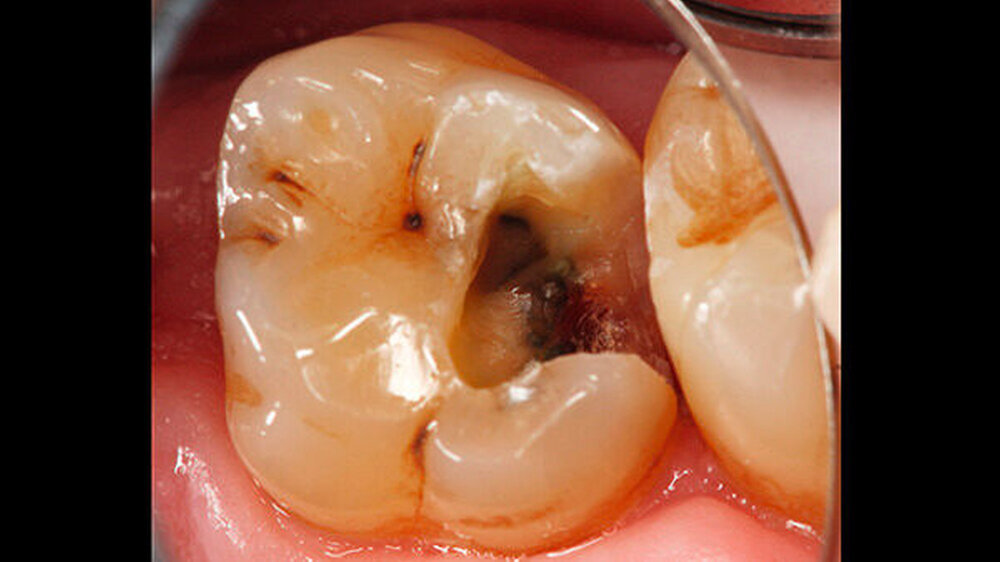

Anschließend erfolgte die Kariesexkavation mit Rosenbohrern unter optischer Kontrolle mit einem OP-Mikroskop. Die Kavität wurde im Verlauf der Exkavation mehrmals mittels FACE (fluoreszenzgestützter Kariesexkavation, SIROinspect, Sirona) auf Residualkaries überprüft [Buchalla W et al., 2013].

Bei der vollständigen Kariesentfernung kam es nicht zu einer Freilegung der Pulpa (Abbildung 3). Anschließend wurde eine Metallmatrize (HaweTofflemire Matrize, Kerr Dental) angelegt und verkeilt. Die Kavität wurde gereinigt und getrocknet.